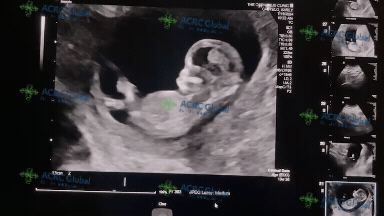

今天是爱妈K的妇产科体检日,胎宝宝已经13周了!一般在14到16周的时候可以看出宝宝的性别。第三代试管婴儿技术不仅能筛查染色体异常,还能通过PGS(胚胎植入前遗传学筛查)和XY优选技术,实现私人定制的生育计划。

此技术不仅帮助了胚胎遗传筛查,还可以帮助准父母选择宝宝的性别。相比其他方法,PGS/PGD的可靠性高达99.99%,几乎可以保证准父母的期望得以实现。我们期待准父母的男宝继续健康成长,实现儿女双全的家庭梦想。